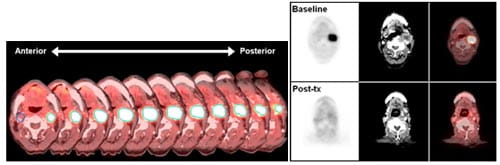

Services offered include an assortment of simplified imaging biomarker procedures depending on the needs of the researcher (Figures 3 and 4). Examples include assessment of static tracer uptake measures such as SUV, maximum SUV, and tumor glycolytic index (in the case of FDG). PET-CT scans of one patient at different therapy time-points can be registered together in order to evaluate therapeutic response over time.

Figure 3. One arm of the TIM analysis laboratory is the development of simplified, clinically practical methods for evaluating early-therapy response in cancers. Here, a 60 year old patient with squamous cell carcinoma of the head and neck (SSCHN) is demonstrating a large 3.3×2.3cm confluent nodal metastasis at left level II. Volumetric method of analysis (left) is performed by drawing a volume of interest (VOI) around the lesion and mirrored contra-lateral region is displayed here in a series of transverse slices. The baseline scan (right, top row) maximum SUV was 17.7 and the post therapy (right, bottom row) maximum SUV was 3 were found with conventional clinical ROI measurements. Total glycolytic index (TGI) was also measured at both time points. At baseline, TGI= 82.2 and decreased to 4.6 at post-therapy, which was within one SD of background FDG activity.